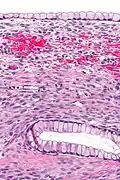

Micrograph showing a mucinous cystadenoma of the ovary. H&E stain.

Microscopy